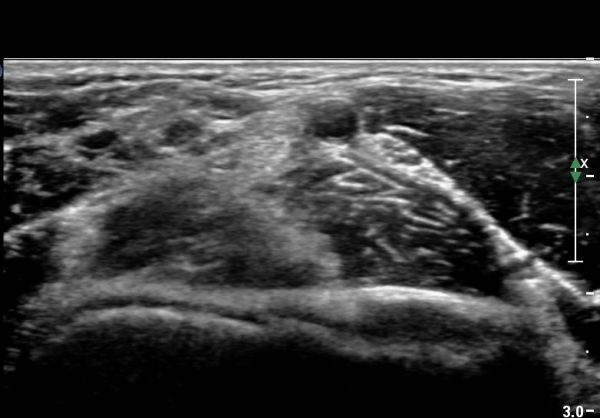

ŽÃËÀÚ¸¦ Á¶±Ý ¸»´ÜÀ¸·Î À̵¿Çϰí ŽÃËÀÚ¸¦ ¸Ó¸®ÂÊÀ¸·Î ±â¿ïÀÌ´Ï À̵ιڱٰÇÀÌ ¶Ñ·ÈÇÏ°Ô °üÂûµÇ´Âµ¥ À̵ιڱٰÇÀÇ ºÎÁ¾ÀÌ °üÂûµÊ(±×¸² 3).